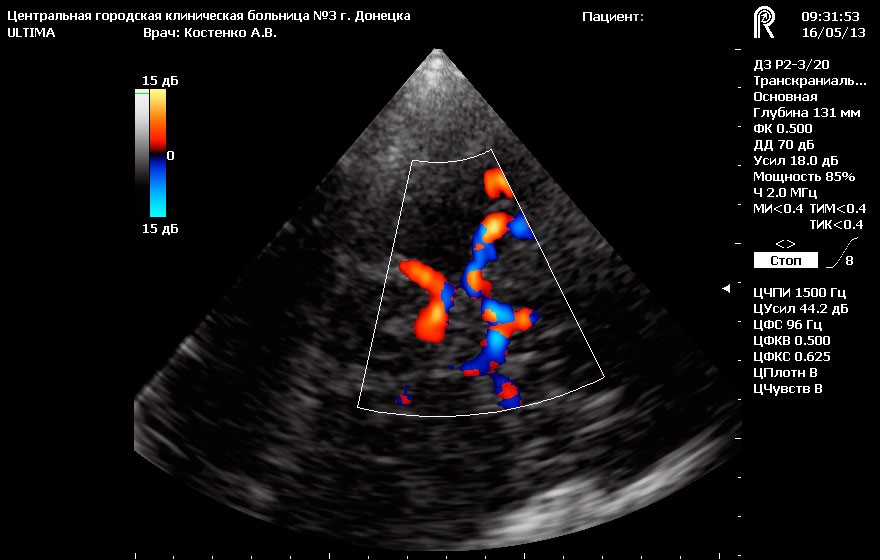

Дуплексное сканирование сосудов основания головного мозга - это исследование артериальных сосудов основания головного мозга бассейна внутренней сонной и позвоночных артерий с проведением функциональных проб и исследованием путей коллатерального кровоснабжения. Также в объем исследования входит исследование путей венозного оттока (у детей – включая кавернозный синус) от глубоких и поверхностных вен головного мозга с проведением функциональных проб.

ТКДС сосудов головного мозга у взрослых методически правильно выполнять только после проведения УЗДС экстракраниального отдела брахиоцефальных сосудов (сосудов шеи, которые несут кровь к головному мозгу).

У детей до 16 лет ТКДС сосудов головного мозга является первым этапом диагностики сосудистой патологии брахиоцефальных сосудов.